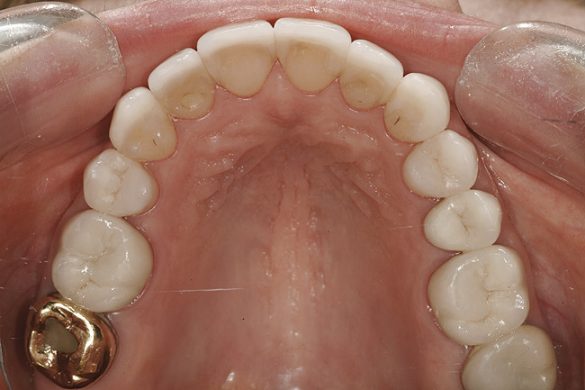

O pacientă în vârstă de 44 de ani s-a prezentat pentru evaluarea şi îmbunătăţirea zâmbetului ei. Acuza principală era reprezentată de afişarea neatractivă a coroanelor posterioare din aur, asociată cu petele albe inestetice de pe dinţii frontali (fig. 1, 2). Scopul ei convingător pentru solicitarea tratamentului a fost acela de a dobândi un „zâmbet deosebit”.

FUNCŢIONAL: La majoritatea dinţilor posteriori ai pacientei ce erau restauraţi cu coroane (fig. 6, 7) era importantă interpretarea minuţioasă a istoricului pacientei şi a rezultatelor evaluării ocluzale. Coroanele din aur de la nivelul 1.7. şi 1.4. prezentau orificii de uzură pe suprafeţele ocluzale, cu semne de minimă uzură pe celelalte coroane posterioare şi la dentiţia naturală. Era evidentă o uzură moderată pe coroana din aur a molarului 4.7.